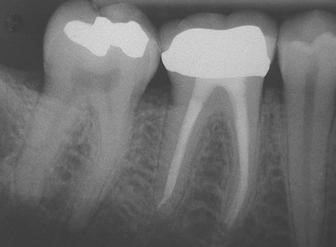

A root canal is a procedure done to treat and save a tooth that is damaged, infected or badly decayed. The treatment involves (1) removal of the nerves and pulp and (2) cleaning and sealing the infected area inside the tooth.